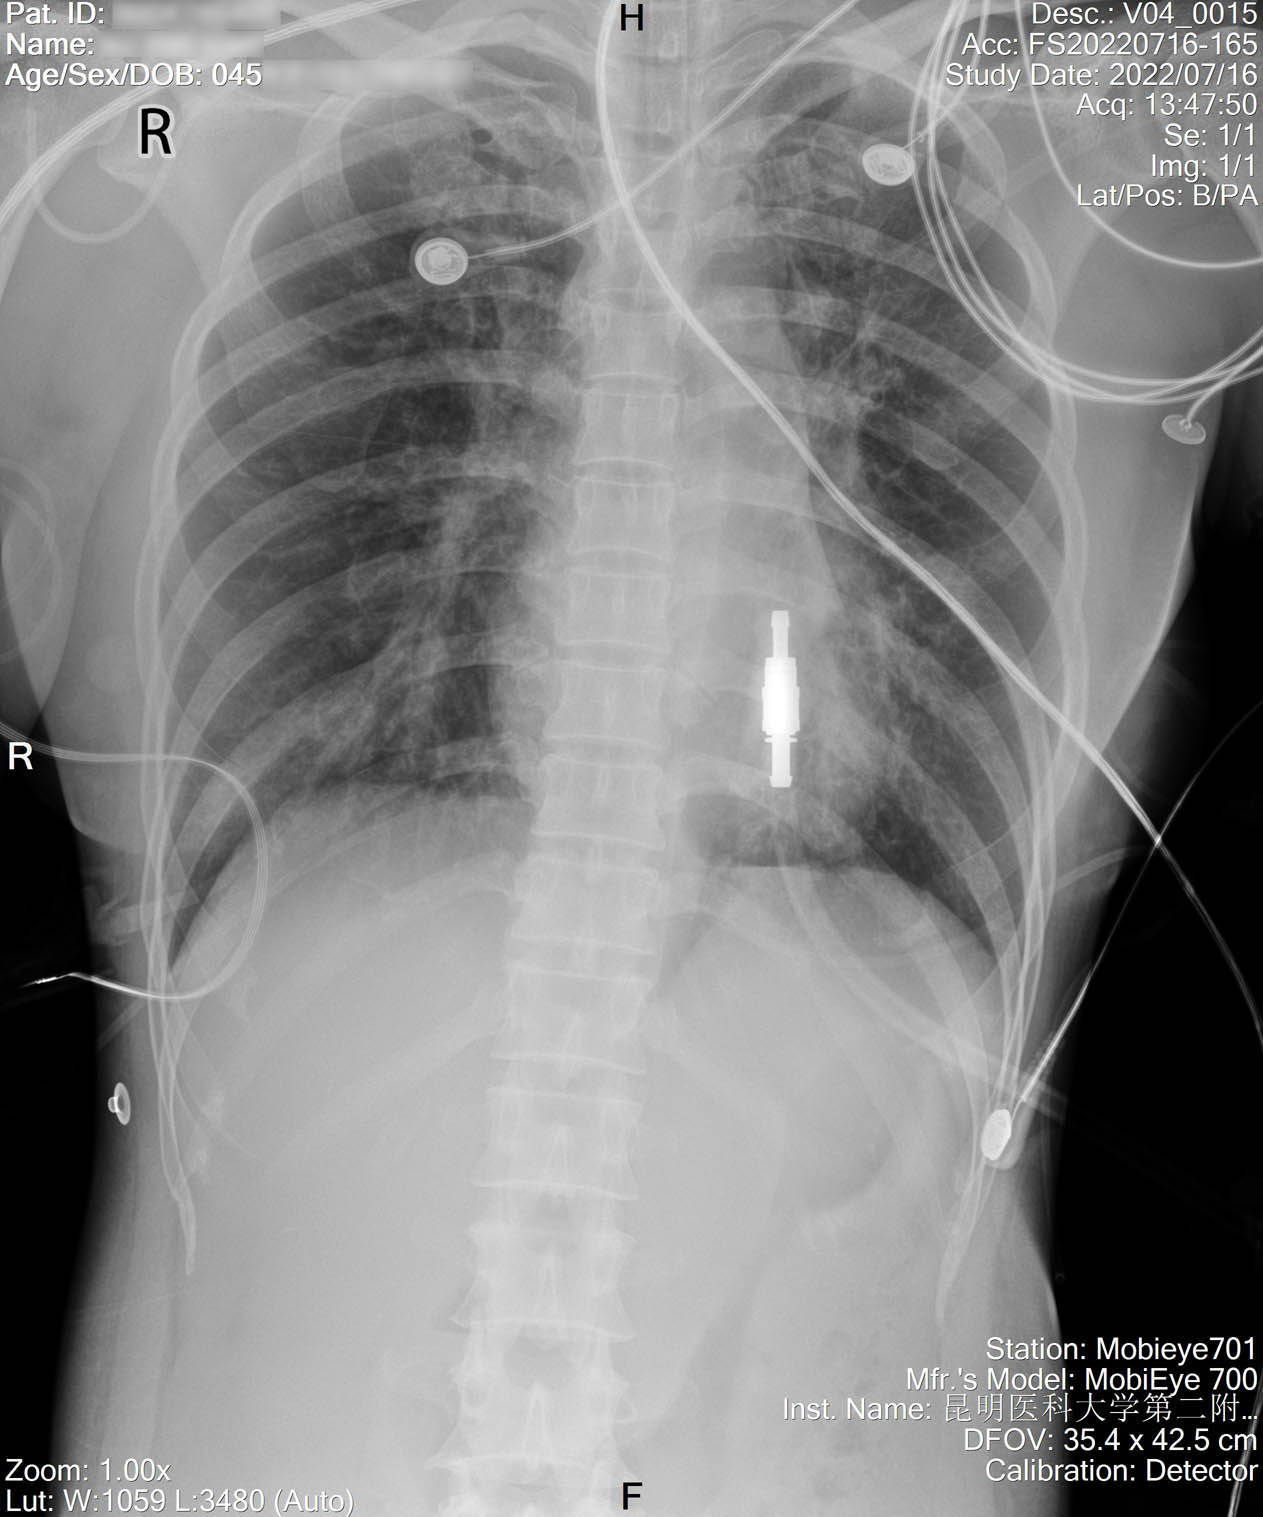

2022-07-19_胸片